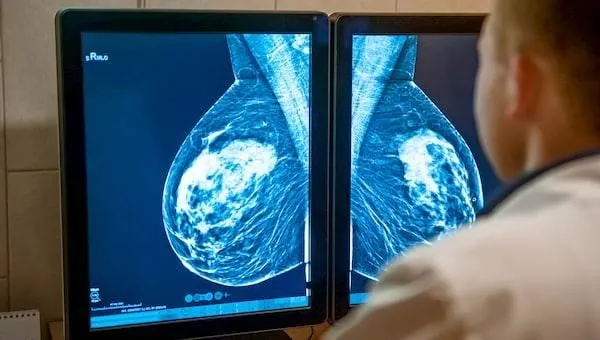

Hiç doğum yapmamak ya da geç doğum yapmak, meme kanseri için risk oluşturuyor. Uzmanlar, tiroit rahatsızlığı bulunan kadınlarda kanser riskinin daha çok arttığını söylüyor.

ABD'de her 8 kadından 1'i, Türkiye'de ise her 12 kadından 1'i meme kanserine yakalanıyor. Hiç doğum yapmamak ya da geç doğum yapmak meme kanseri için risk oluşturuyor.

Tiroit ile ilgili rahatsızlığı bulunan kadınlarda meme kanseri görülme oranı daha yüksek olabiliyor. Doç. Dr. Fatih Levent Balcı, meme kanseri hakkında önemli bilgiler veriyor:

Meme kanseri, kadınlardaki kanserlerin tümünün yüzde 33'ünden ve kanserle ilişkili ölümlerin yüzde 20'sinden sorumludur.

Meme kanseri erken dönemde yakalandığında yüzde 95'e yakın oranda başarı ile tedavi edilebilmektedir. Genelde memede ele gelen kitle kanseri düşündürtse de, her ele gelen kitle kanser anlamına gelmemektedir. Kadınların öncelikle ayda bir ayna karşısında rutin meme muayenelerini yapmaları gerekmektedir.

Meme kanseri olan hastaların birçoğunda tiroit nodülü saptanabilir. Bu tiroit nodülleri incelendiğinde %10-15 oranında tiroit kanseri olduğu saptanmıştır. Meme kanseri olup tiroit nodülüne sahip olan hastaların ileriki dönemde tiroit kanserine yakalanma riski yüksektir. Tiroit kanseri olanlarda meme kanseri olma riski 1.5-2 kat artar.